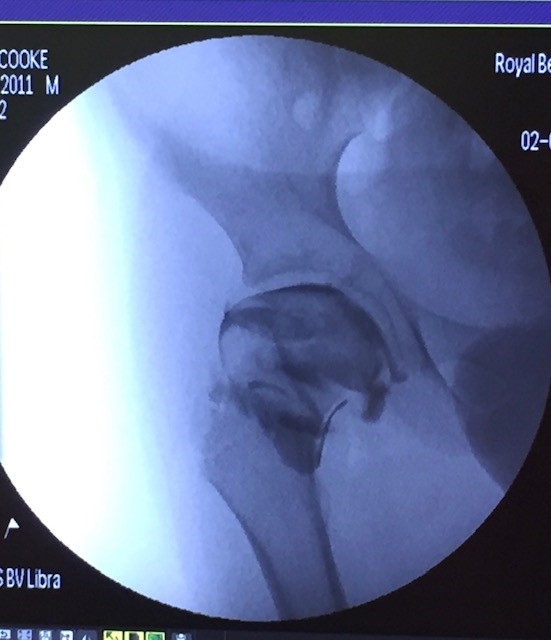

Arthrogram2

The arthrogram image